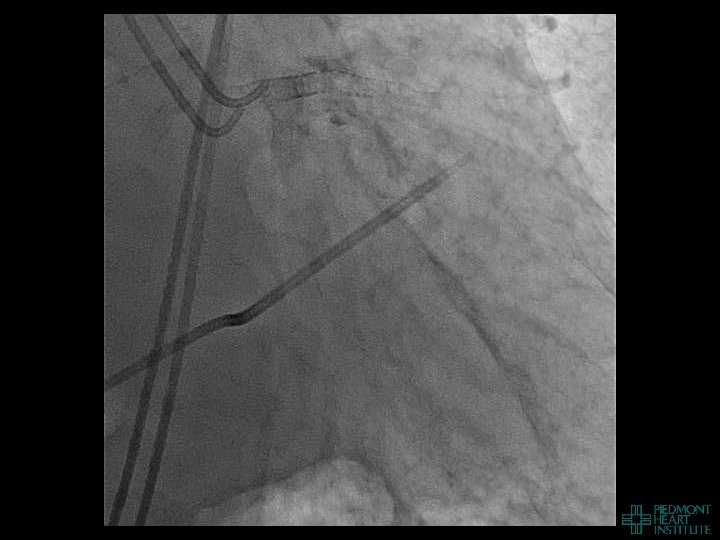

Day 2 No further pericardial drainage, echo without effusion…pericardial catheter pulled Day 3 Enoxaparin

Day 2 No further pericardial drainage, echo without effusion…pericardial catheter pulled Day 3 Enoxaparin for DVT prophylaxis initiated 8 hours later, PEA arrest Echo shows recurrence of effusion and tamponade physiology

Case Example 4